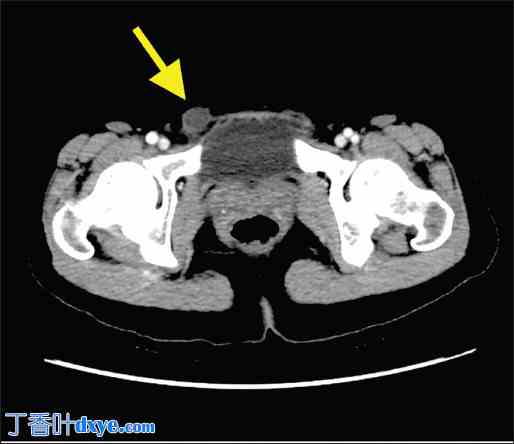

图1

1.jpg

轴位增强腹部CT扫描。右侧腹股沟囊实性肿块(黄色箭头)。